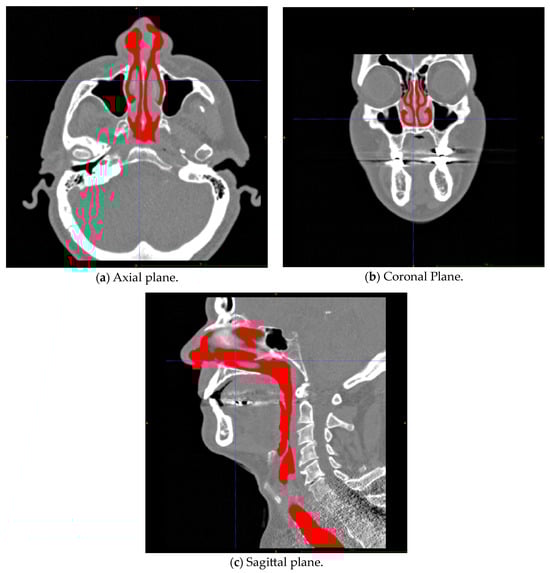

- Automatic segmentation methods may overlook important details or include secondary air spaces such as the paranasal sinuses, Eustachian tubes, or nasolacrimal ducts. It is recommended to confer with medical expertise such as radiology experts or surgeons to assess the resulting geometry model.

4.1.2. Geometry Retrieval